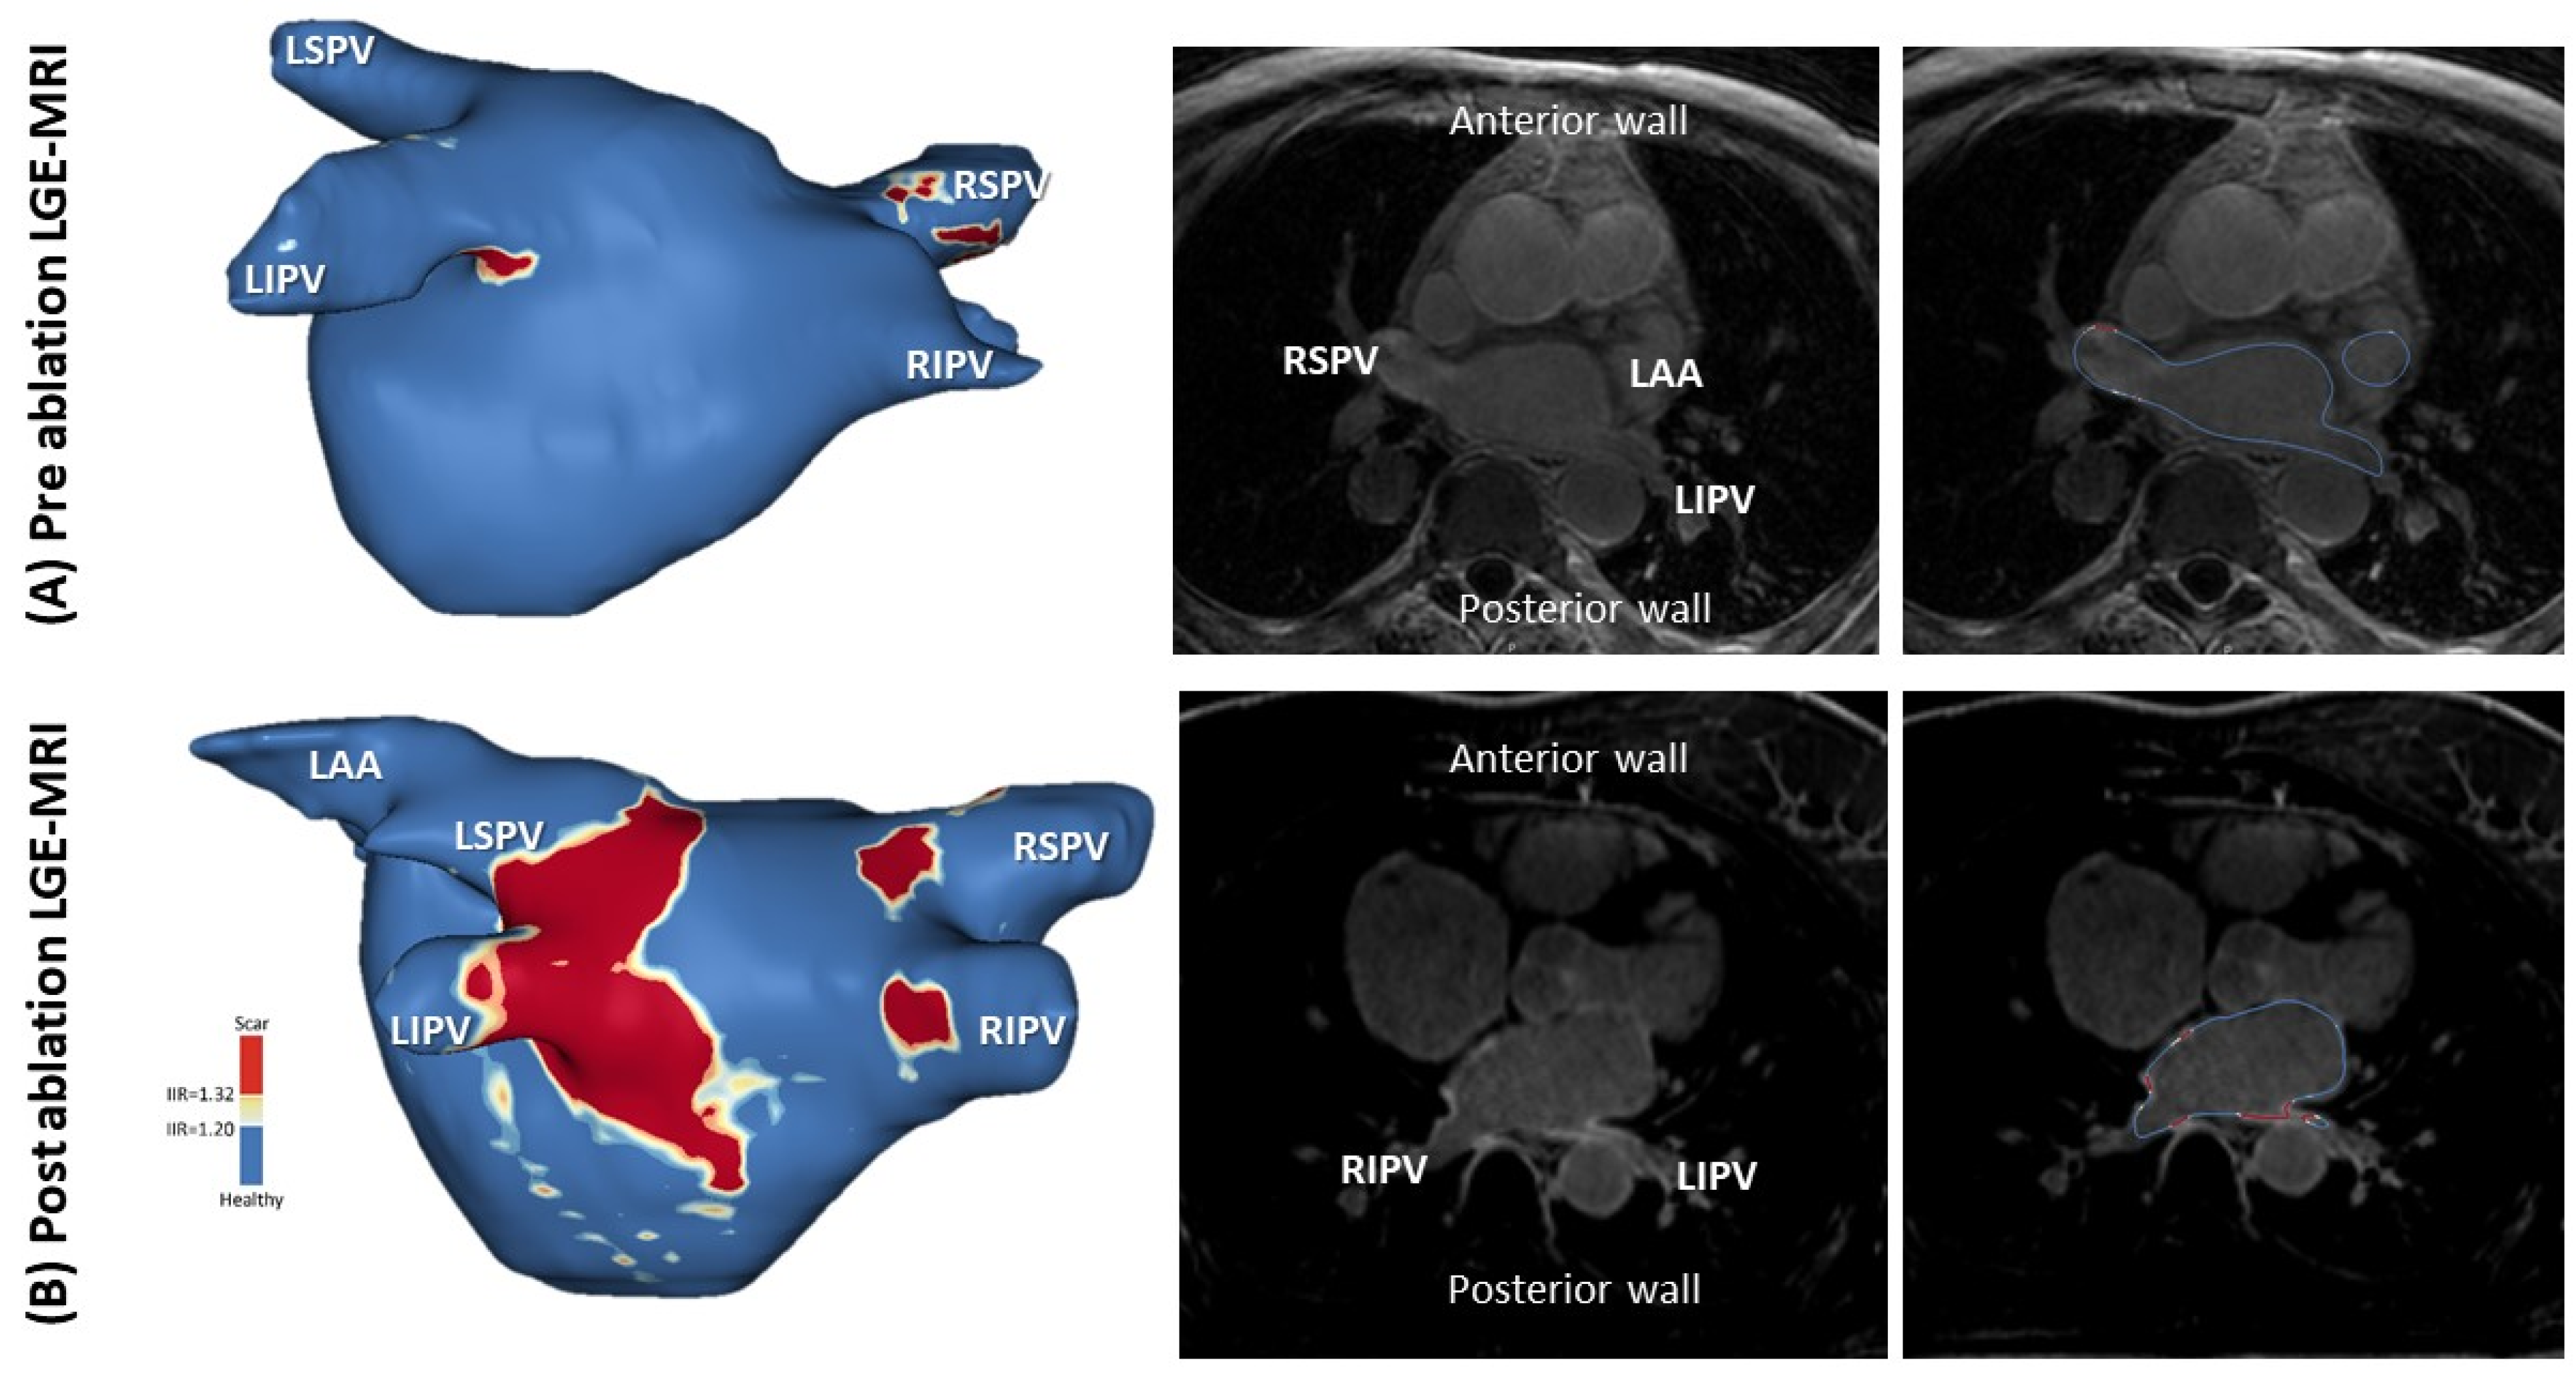

4.4. LGE-MRI for AF Ablation

- Bisbal, F.; Guiu, E.; Cabanas-Grandío, P.; Berruezo, A.; Prat-Gonzalez, S.; Vidal, B.; Garrido, C.; Andreu, D.; Fernandez-Armenta, J.; Tolosana, J.M.; et al. CMR-guided approach to localize and ablate gaps in repeat AF ablation procedure. JACC Cardiovasc. Imaging 2014, 7, 653–663. [Google Scholar] [CrossRef] [Green Version]

- Quinto, L.; Cozzari, J.; Benito, E.; Alarcón, F.; Bisbal, F.; Trotta, O.; Caixal, G.; Antonio, R.S.; Garre, P.; Prat-Gonzalez, S.; et al. Magnetic resonance guided re-ablation for atrial fibrillation is associated with a lower recurrence rate: A case-control study. Europace 2020, 22, 1805–1811. [Google Scholar] [CrossRef]

- Linhart, M.; Alarcon, F.; Borras, R. Delayed gadolinium enhancement magnetic resonance imaging detected anatomic gap length in wide circumferential pulmonary vein ablation lesions is associated with recurrence of atrial fibrillation. Circ. Arrhythm. Electrophysiol. 2018, 11, e006659. [Google Scholar] [CrossRef]

- Badger, T.J.; Daccarett, M.; Akoum, N.W. Evaluation of left atrial lesions after initial and repeat atrial fibrillation ablation: Lessons learned from delayed-enhancement MRI in repeat ablation procedures. Circ. Arrhythm. Electrophysiol. 2010, 3, 249–259. [Google Scholar] [CrossRef] [Green Version]